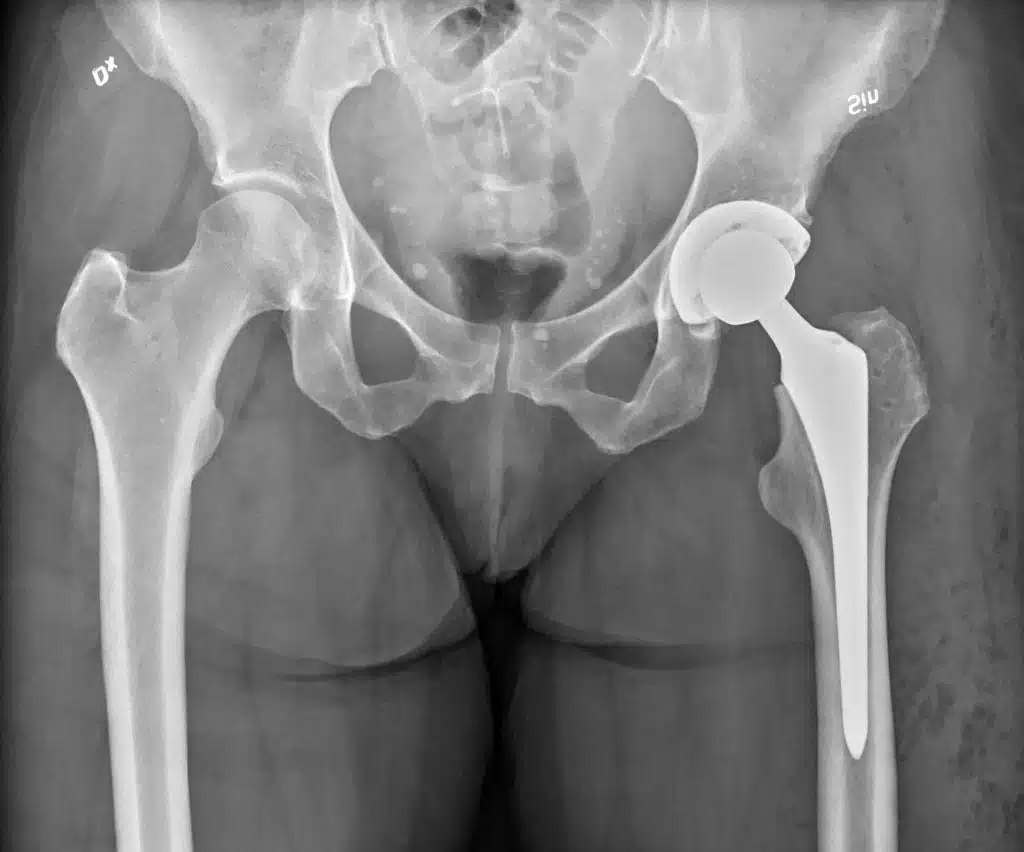

أولاً: الاستبدال الكلي

في حالات التلف الكامل أو التهابات المفاصل المتقدمة أو كسور الورك المعقدة يكون من الضروري إزالة المفصل الأصلي بالكامل وزراعة مفصل صناعي مكانه، فهذه العملية تسمح للمريض باستعادة قدرته على المشي والحركة بثبات.

المفصل الصناعي يُصمم ليُحاكي دقة حركة المفصل الطبيعي ويُثبت في موضعه باستخدام تقنيات حديثة تضمن ثباته ومتانته على المدى الطويل، ويعتمد نجاح العملية إلى حد كبير على التأهيل بعد الجراحة مثل العلاج الطبيعي الذي يساعد على استعادة الحركة بشكل تدريجي وآمن.